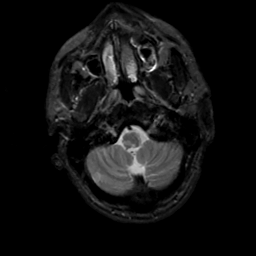

MR Study #5, March 10, 1991 -- Slice #7